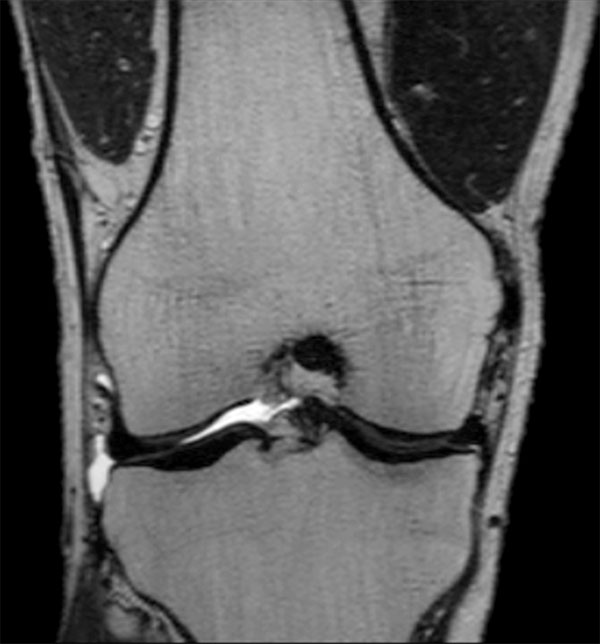

Comprehensive 3D knee imaging with MSK VIEW